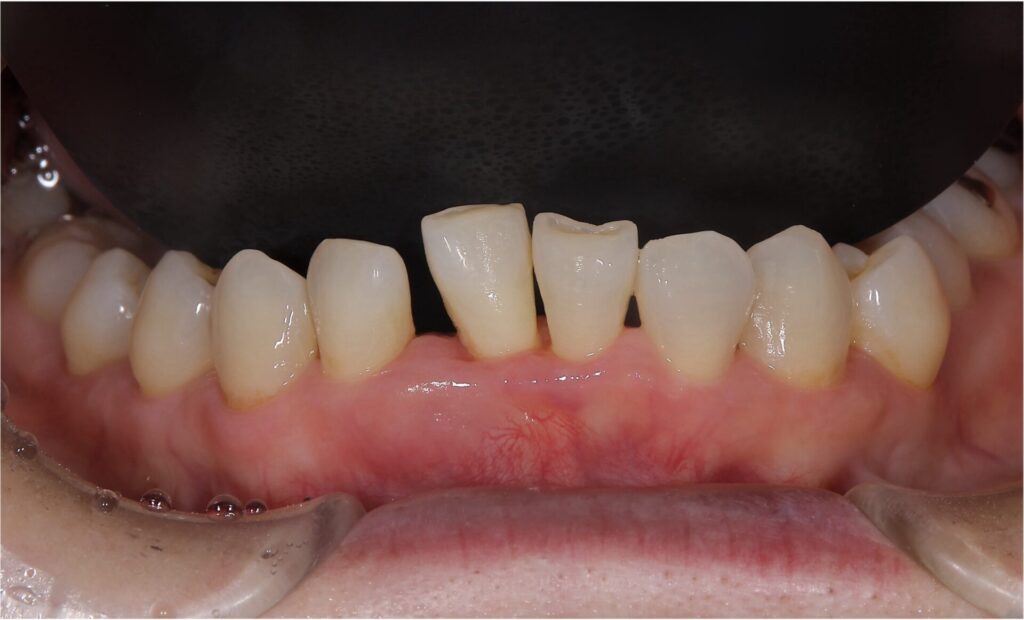

今回の患者様は右下の前歯(向かって真ん中左の歯)が歯周病が進行してしまい抜歯と判断いたしました

治療の前後の比較写真です

残念ながら抜歯となってしまった歯ですが、隣接する歯を削ることなく審美的に治療を終えることができました